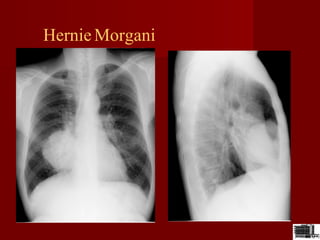

Hernie Morgani